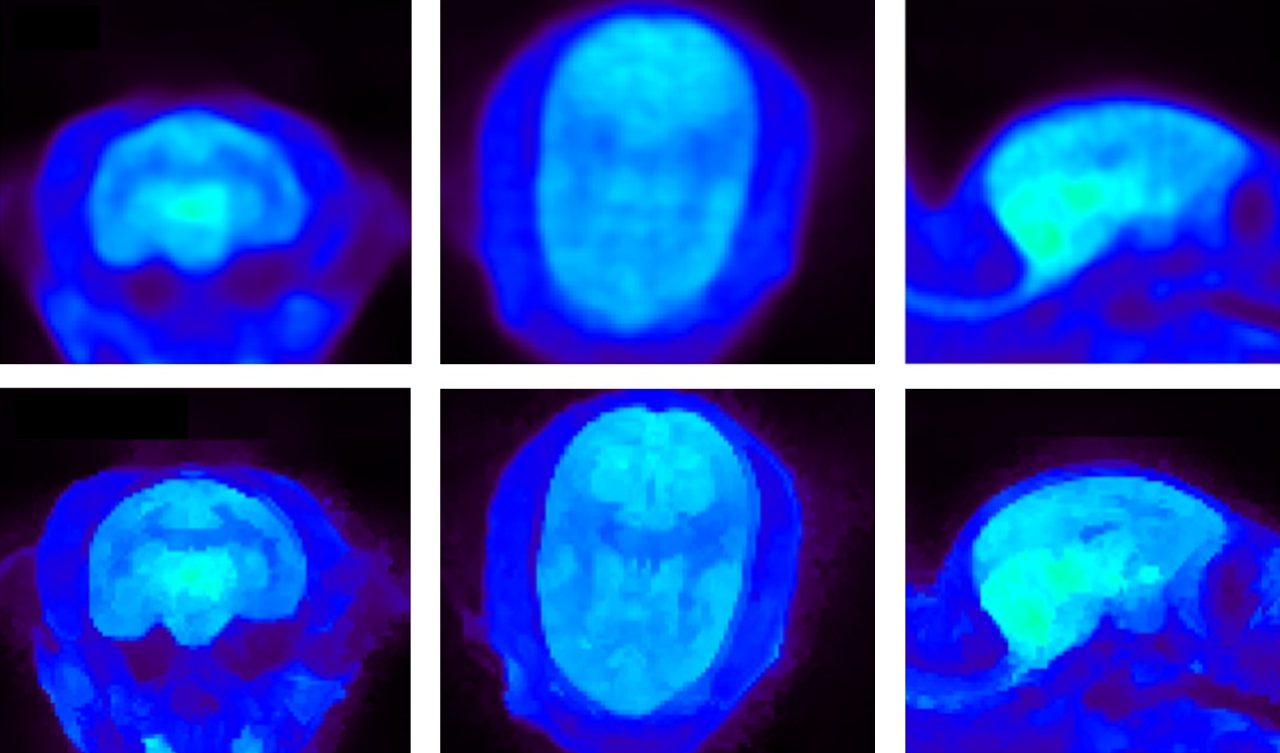

Marmoset brain imaging with PET FDG. Top: MAP reconstruction. Bottom: Bowsher Prior reconstruction, an advanced PET reconstruction algorithm. Courtesy: S. Valable and M Naveau, Cyceron, Caen, France.